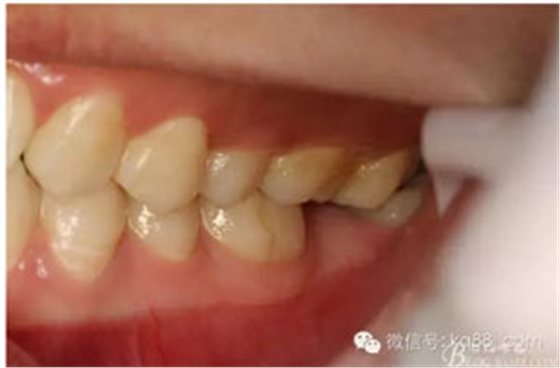

圖2.術(shù)前口內(nèi)照:37未萌出。38牙冠近中傾斜。患者粘膜色澤正常,無瘺管、無滲出。

圖3。閉口位,27與38有咬合接觸。因此,保留38、拔除37.防止囊性變進一步擴大。